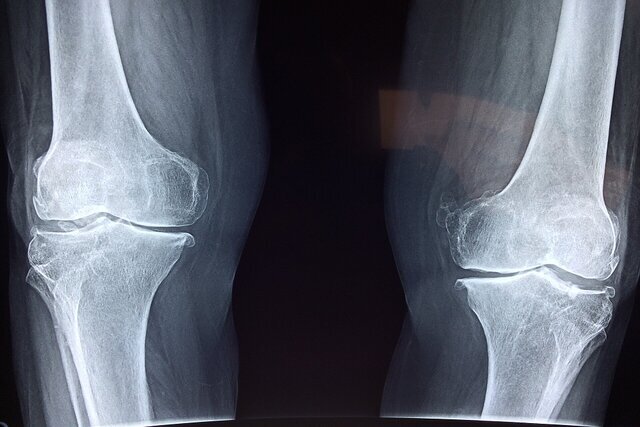

رئیس اورژانس پیش‌ بیمارستانی و مدیریت حوادث دانشگاه علوم پزشکی کرمانشاه درباره افزایش خطر شکستگی‌ استخوان در فصل زمستان و خصوصا روزهای یخبندان هشدار داد و گفت: سالمندان و کودکان از مهمترین گروه‌های در معرض خطر هستند.